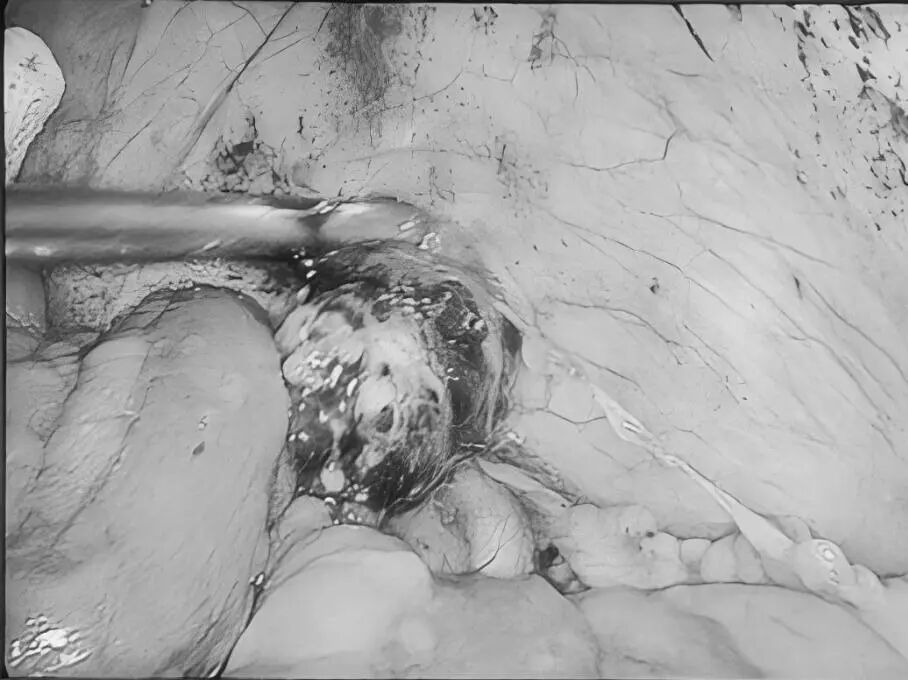

“医生,我爸妈只是关节痛,吃了点止痛药,怎么会胃穿孔要手术?”在普外科病房里,这样的疑问屡见不鲜,很多儿女都困惑不已:明明只是想帮老人缓解疼痛,一片孝心,怎么会把父母送进手术室? 今天,贵州航天医院普外科就来和大家聊聊如何科学、安全地使用止痛药,保护我们脆弱的胃肠,享受健康的生活! 【止痛药咋就把胃吃穿了?】 把胃想象成一个气球,胃黏膜就是内壁,很多止痛药(比如布洛芬、双氯芬酸钠等)会削弱这层内壁,胃酸就像强酸,没了胃黏膜这层内壁保护就会直接腐蚀胃,轻则糜烂、溃疡,重则出血、穿孔。 最危险的是:胃穿孔早期可能只是隐隐作痛、有点胀,容易被当成“老胃病”扛过去,等剧痛发作时,胃里的东西已流进腹腔,危及生命。 【为啥受伤的总是老年人?】 ※胃功能减退:上了年纪,胃黏膜变薄、修复能力下降。 ※多种药同吃:很多老人同时服用降压药、抗凝药,和止痛药叠加,胃根本扛不住。 ※自行用药:怕麻烦不去医院,按老经验或邻居推荐买药,隐患最大。 【安全用药“四要、四不要”】 四要—— ✔要查明原因:疼痛是警报,先看病再吃药,别盲目止痛。 ✔要保护胃:在医生指导下可加用胃黏膜保护剂(如奥美拉唑)。 ✔要饭后吃:务必饭后半小时服用,减少刺激。 ✔要见好就收:不疼了就停药,绝不长期吃。 四不要—— ❌不要自己加量:疼得厉害?找医生,别加药。 ❌不要混着吃:不同止痛药一起吃等于伤害叠加。 ❌不要长期吃:一般疼痛不连续吃超过一周。 ❌不要忽视警报:出现胃部不适、黑便、呕血、剧烈腹痛,立即停药就医! 【对付慢性疼痛,还有其他好办法】 ▶热敷、冷敷:简单有效,很多肌肉关节痛都管用。 ▶理疗、按摩:找正规中医推拿,效果不输止痛药。 ▶温和运动:散步、打太极,增强肌肉力量。 ▶转移注意力:养花、写字、聊天——当你不那么关注“痛”时,痛感往往会减轻。 【给子女的2点提醒】 ※管好药箱:定期清理过期药,搞清楚老人每天在吃什么药。 ※当好翻译:陪老人看病时,说清哪里痛、吃过啥药、效果如何。 止痛药是缓解疼痛的有效工具,但绝非“万能神药”。请一定记住:面对疼痛,“硬扛”不是办法,“乱吃”更是大忌,守护胃肠健康,从科学用药开始。 注:本文仅为健康科普,旨在提高公众用药安全意识,具体用药请务必咨询专业医生,遵医嘱执行。 贵州航天医院普外科专家简介 高大勇 普外科(肛肠外科)学科带头人、名誉主任,主任医师、教授 临床擅长:对中西医结合诊治肛肠学科各种常见病、多发病及疑难杂症等具有丰富的临床经验。 原遵义市第一人民医院(遵义医科大学第三附属医院)、遵义市中医院肛肠科主任。中华中医药学会肛肠分会常委,全国中医肛肠学科名专家,中国健康促进与教育协会肛肠分会常委,中国康复医学会肛肠疾病康复专业委员会常委,中国民间中医医药研究开发协会肛肠分会副秘书长,中国医师协会中西医结合肛肠医师专业委员会常委,国家二级心理咨询师,贵州省第一批中医名医工作指导老师,遵义市名中医,遵义市肛肠学会会长,遵义市肛肠质控中心名誉主任,遵义市中西医结合学会名誉会长,遵义市健康科普专家,原贵州省中西医结合学会肛肠分会副主任委员、贵州省中医肛肠质控中心副主任、遵义市医学会医疗鉴定委员会专家、遵义市卫生系列高评委。发表论文30余篇,主编和参编医学著作5本,主持省级科研课题2项、市级科研课题2项、院级科研课题1项。 梁 跃 普外科党支部书记、主任,主任医师 临床擅长:对普外科各类肿瘤手术具有丰富的临床经验。 毕业于遵义医学院,遵义市医学会小儿外科学分会常务委员,遵义市肛肠协会理事,遵义市医学会核医学分会(第二届)委员会委员;荣获第三期“黔医人才计划”优秀学员称号;主持市级课题1项,完成省级课题1项,在国内各类刊物上发表论文10余篇。 钱科洪 民盟盟员,普外科副主任医师 临床擅长:从事普外科临床工作30余年,对各类普外科疾病的诊治、乳腺、甲状腺、胃十二指肠、结直肠等疾病及疑难杂症具有丰富的临床经验。 毕业于遵义医学院临床医疗系,2009年前往中山大学附属第一医院微创外科进修学习,在国内各专业期刊发表论文数篇。 贵州航天医院普外科简介 基本情况 贵州航天医院普外科成立于1968年,前身属于航天部O61基地3417医院外一科,1998年3417医院、3427医院合并后更名为普外科,下设胃肠外科、肛肠外科2个亚专业科室,拥有在全市较为先进的专科设备和技术,是中国疝病专科联盟单位,贵州医科大学附属医院胃肠外科专科联盟单位。开放床位40张,配备医护人员21人。 专科特色 普外科致力于胃肠及肛肠疾病的外科临床诊治及科研,以腹腔镜微创外科技术为本,形成以快速康复治疗胃肿瘤、结直肠肿瘤、小肠肿瘤、直肠脱垂、肥胖病、急腹症、各类疝、痔、瘘等专科特色,同时注重胃肠疾病尤其是结直肠恶性肿瘤的基础研究和临床转化研究,总体诊断和治疗水平在区域同级医院居于领先水平。 开展手术:腹腔镜下胃癌根治术,腹腔镜下袖状胃切除术,腹腔镜下胃肠道间质瘤切除术,腹腔镜下结、直肠癌根治术,胃癌、结直肠癌的精准治疗,腹腔镜下小儿疝气、成人疝修补术,腹腔镜下阑尾手术,内痔的硬化注射治疗及痔疮的微创治疗:ATH、PPH、TST,直肠脱垂的各种手术治疗,难治性伤口VSD技术,鼻胃肠管、肠梗阻导管置入术,肛肠术后间歇性导尿技术,并引进了中医适宜技术,也为各种化疗患者提供输液港安装,提高患者就医体验。 腹腔镜下腹股沟疝 无张力修补术 腹股沟疝里金斯坦 (Lichtenstein)手术 PPH微创术治疗环状混合痔 黏连性或炎性肠梗阻-肠梗阻导管 腹腔镜袖状胃切除 腹腔镜阑尾切除术 腹腔镜阑尾肿瘤切除术 腹腔镜下结肠癌根治术 诊疗范围 胃肿瘤、结直肠肿瘤、小肠肿瘤、肥胖症、各类急腹症、腹部外伤、腹壁疝、便秘、直肠脱垂、痔疮、肛瘘、肛裂等胃肠、肛肠外科疾病。 END